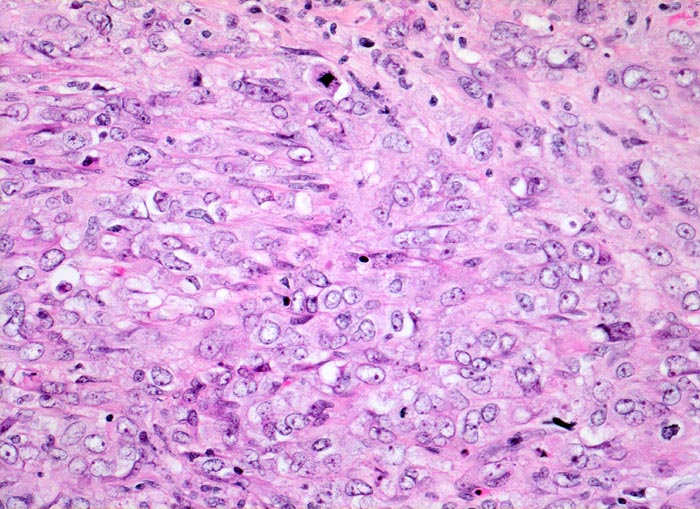

Chronische Niereninsuffizienz bei bekanntem jahrelangem Analgetikaabusus. Inoperables Urothelkarzinom der Harnblase. Weitere Urothelkarzinome in beiden Ureteren. Die Patientin stirbt am metastasierenden Tumorleiden.